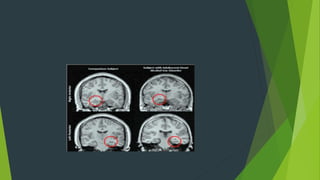

 Los adolescentes que toman alcohol de forma abusiva tienen un

hipocampo (órgano del cerebro encargado de la memoria) 10% más

pequeño en comparación con jóvenes que no toman nunca, lo cual se

evidencia en dificultades para aprender y almacenar nueva

información.

 Tomado de: Bellis MD, Clark DB, Beers SR. Hippocampal volume in

adolescent-onset alcohol use disorders. Am J Psychiatry. 2000; (1

 Esta imagen muestra la actividad cerebral durante un

ejercicio de memoria en un joven de 15 años que no

consume alcohol, comparada con la actividad cerebral de

otro que sí lo hace.

 Puede verse como el cerebro del joven que no toma (el de

la izquierda) tiene muchas más partes del cerebro

activadas mientras recuerda cosas.